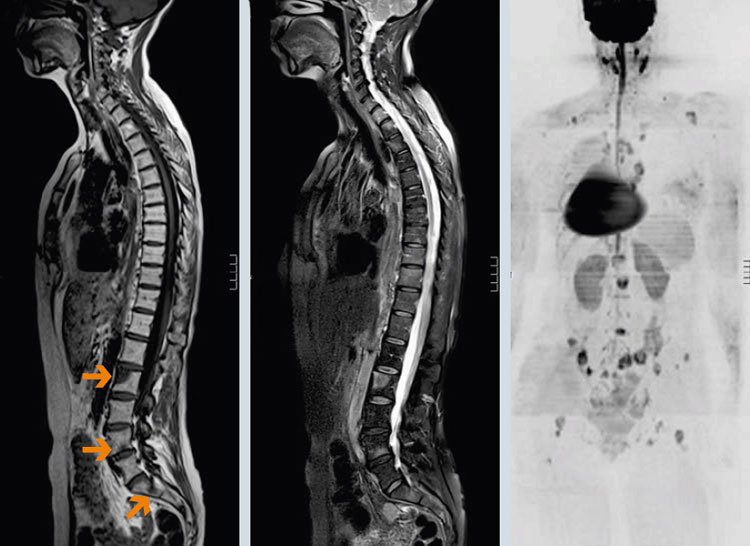

Если сравнивать УЗИ с другими передовыми технологиями – КТ и МРТ, здесь тоже имеются отличия. Хоть по способу исследования (технологически) это новые методы, но они не настолько информативны, как ультразвук. Основаны компьютерные исследовательские методики на магнитном резонансе, и с их помощью можно оценивать состояние околопозвоночных тканей, дисков – преимущественно костной структуры. Состояние внутренних органов гораздо яснее может представить ультразвуковое изображение.

Кстати. С ультразвуком детально рассмотреть плотную костную структуру не получится, но проанализировать состояние мягких тканей он позволит как нельзя лучше. По итогам выполнения процедуры врач получит информацию о связках, соединительных и хрящевых структурах, суставах, дисковых сегментах и патологиях «притаившихся» там.

МРТ позвоночника

УЗИ-исследование даст возможность выявить остеохондрозные изменения, грыжевые образования, степени сколиотических искривлений и даже врожденные пороки развития позвоночных структур.